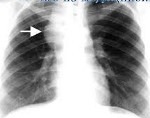

Лимфогранулематоз средостения на начальных этапах протекает с минимальной симптоматикой. Нередко увеличение медиастинальных узлов, выявленных с помощью рентгенографии грудной клетки, является единственным признаком заболевания. Начальные клинические проявления обычно включают недомогание, повышенную утомляемость, бессонницу, пониженный аппетит, похудание. Характерны периодические подъемы температуры тела, сухой кашель, потливость по ночам, кожный зуд. В поздних стадиях ходжкинской лимфомы средостения развивается компрессионный синдром, вызванный сдавлением структур средостения. Клиническим выражением этого синдрома может служить одышка, тахикардия, нарушение глотания, осиплость голоса, одутловатость шеи и лица (синдром верхней полой вены). При осмотре часто определяется увеличение шейных и подмышечных лимфоузлов, выбухание грудной клетки, расширение подкожных вен на груди.

Лимфомы медиастинальной локализации не всегда диагностируются при рентгенологическом обследовании. Компьютерная томография, более детально, чем обзорная рентгенография позволяет рассмотреть конгломерат опухоли, увеличение лимфоузлов средостения, вовлечение паратрахеальных, трахеобронхиальных, прикорневых лимфатических узлов. Диагностическая значимость магнитно-резонансной томографии в верификации лимфом средостения признается не всеми авторами.